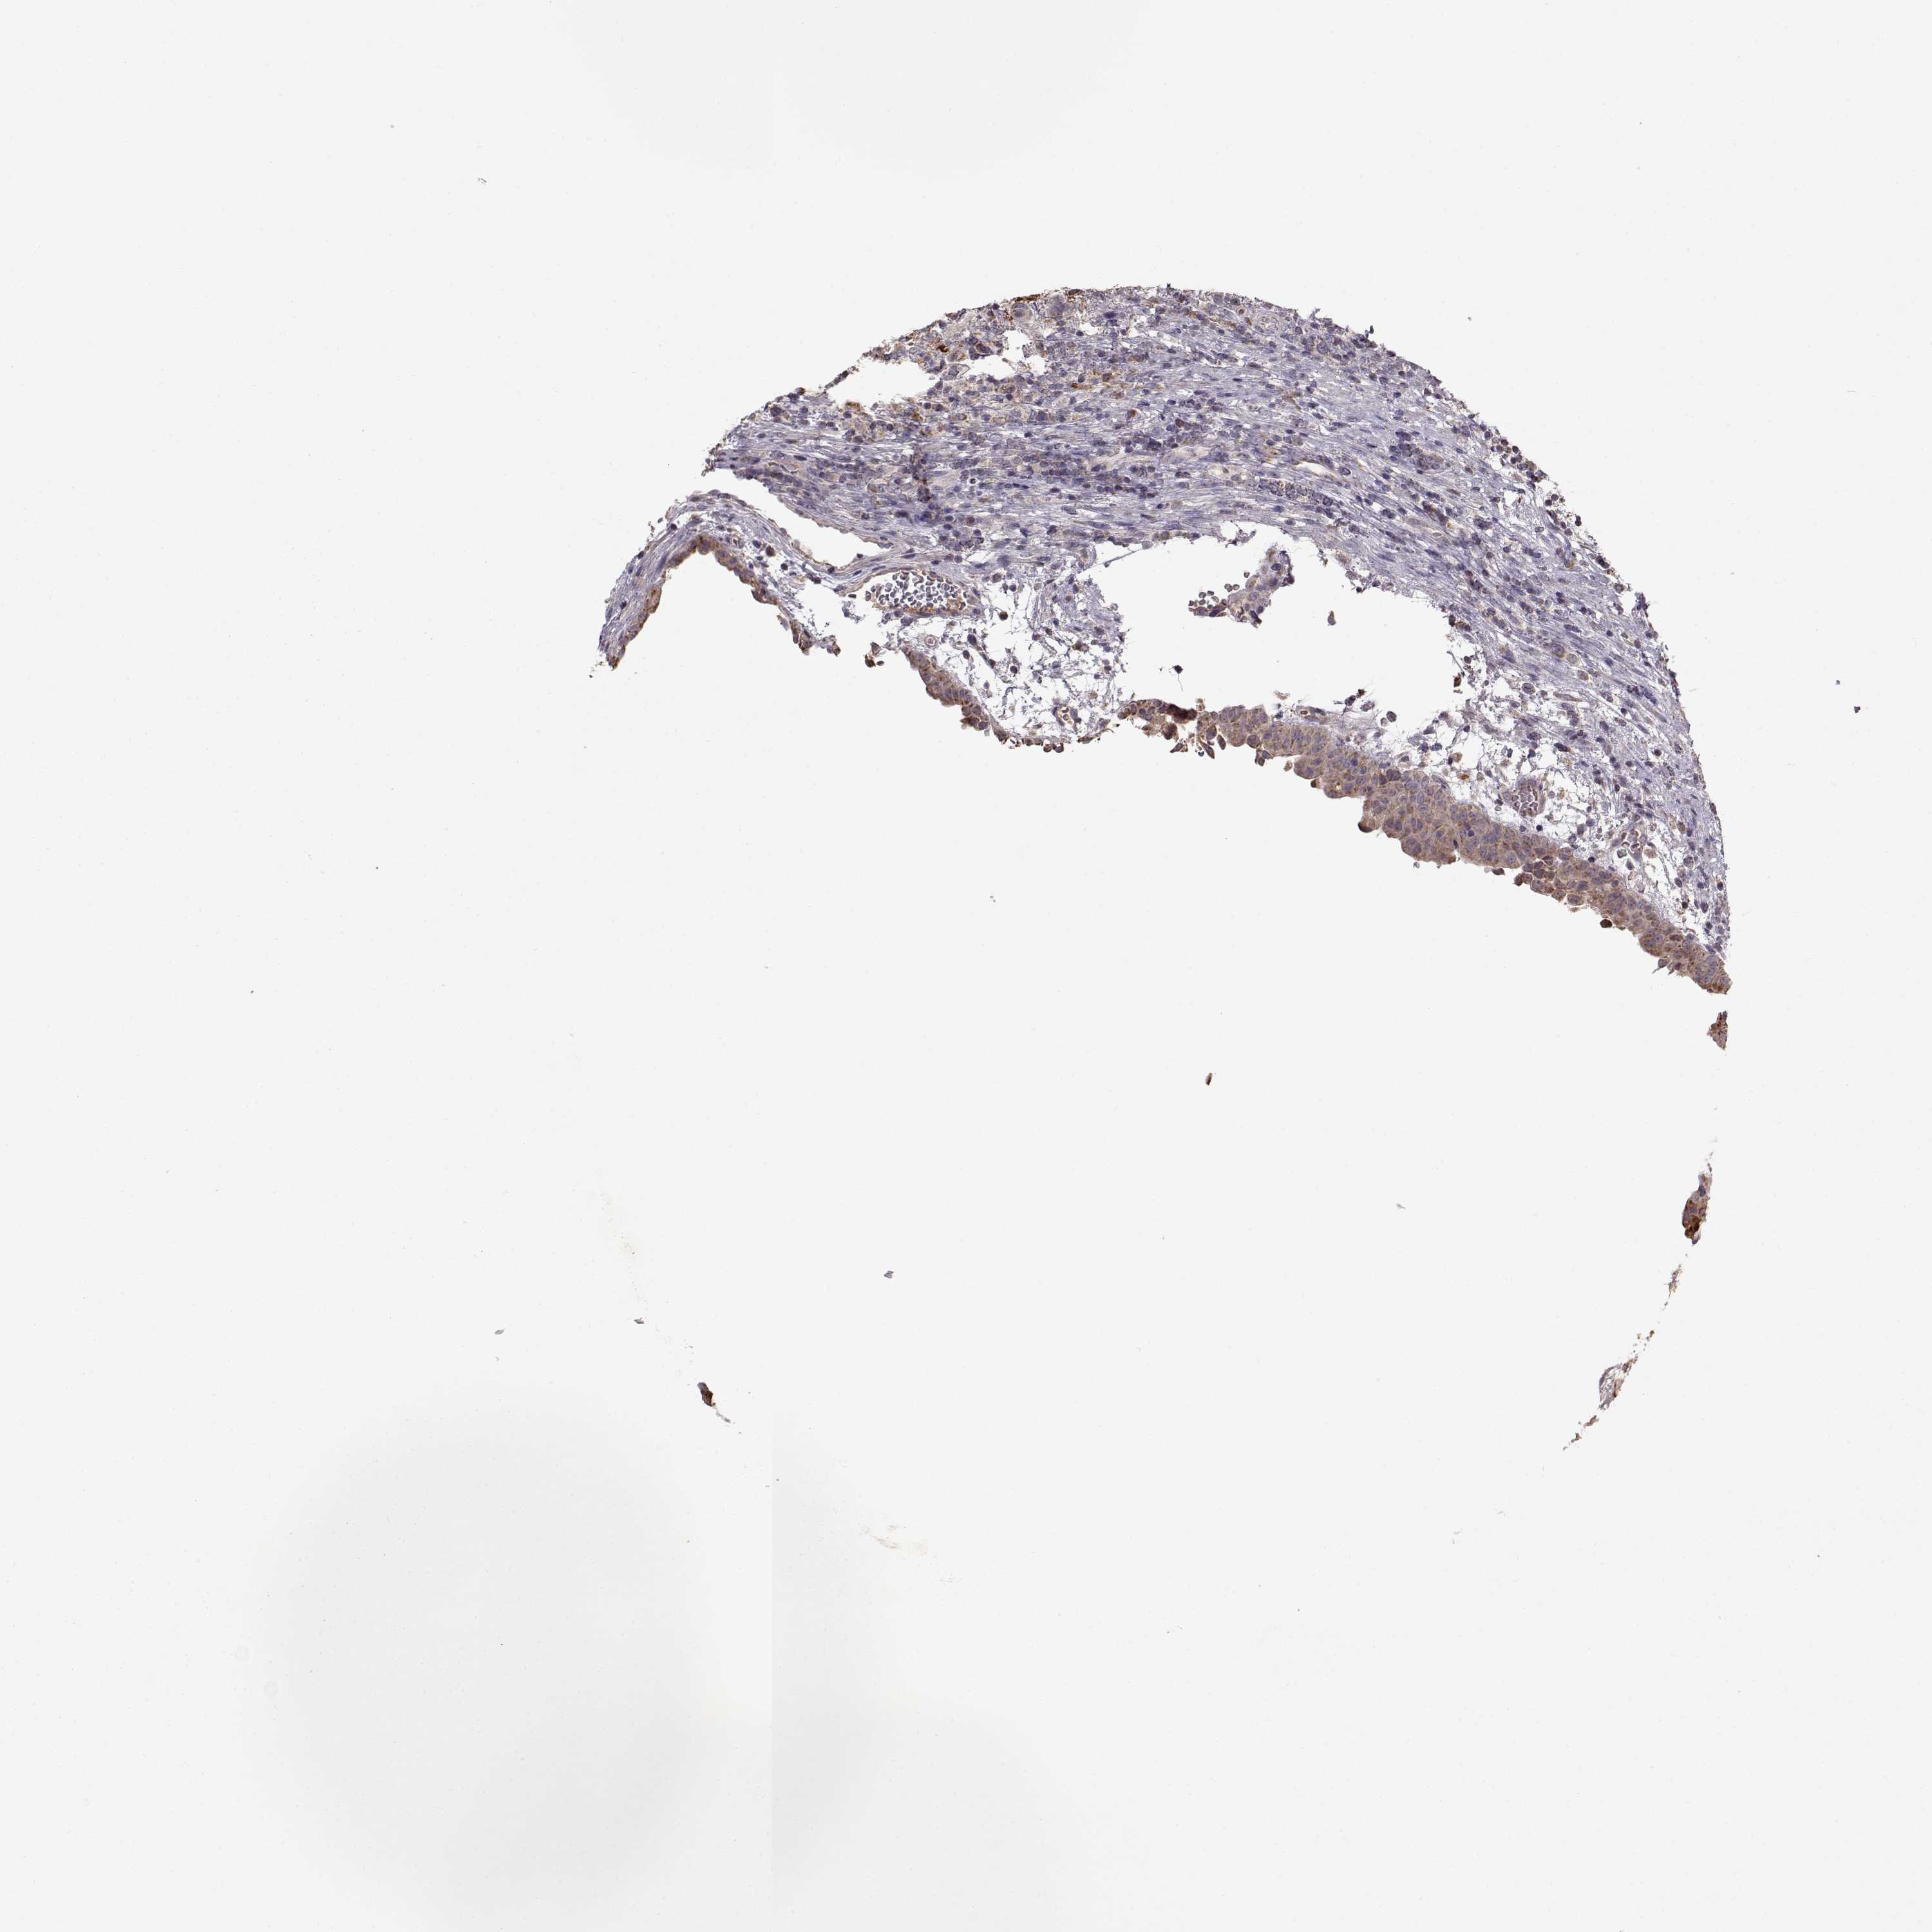

UROTHELIAL CANCER - Protein expressioni

A mouse-over function shows sample information and annotation data. Click on an image to view it in a full screen mode. Samples can be filtered based on level of antibody staining by selecting one or several of the following categories: high, medium, low and not detected. The assay and annotation is described here.

Antibody stainingi

Antibody staining in the annotated cell types in the current human tissue is reported as not detected, low, medium, or high, based on conventional immunohistochemistry profiling in selected tissues. This score is based on the combination of the staining intensity and fraction of stained cells.

Each image is clickable and will lead to virtual microscopy that enables deeper exploration of all samples and also displays staining intensity scores, fraction scores and subcellular localization as well as patient and tissue information for each sample.

Antibody HPA072695

Staining

High

Medium

Low

Not detected

Intensity

Strong

Moderate

Weak

Negative

Quantity

>75%

75%-25%

<25%

None

Location

Nuclear

Cytoplasmic/membranous

Cytoplasmic/membranous,nuclear

Urothelial carcinoma, High grade

Urothelial carcinoma, NOS

Urothelial carcinoma, Low grade